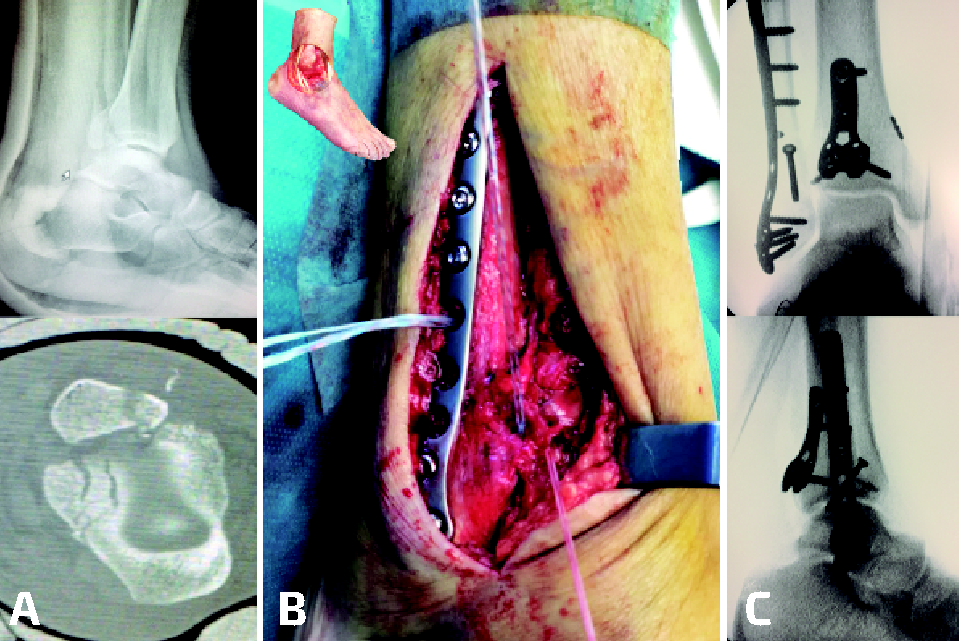

Las ventajas de la reparación anatómica son indudables, dado que proporciona reducciones mucho más precisas y estables, de forma que se puede obviar la necesidad de dispositivos transindesmales ahorrando costes y la necesidad de reintervenciones para la retirada de los mismos(27,28); sin embargo, también se encuentran una serie de desventajas, como el aumento del tiempo quirúrgico por la mayor agresividad de los abordajes o la necesidad de cambiar de posición al paciente durante la cirugía. Para minimizar esta posibilidad, nosotros utilizamos el abordaje posterolateral en decúbito prono cuando no se prevé necesario reparar fragmentos dependientes del LTFAI y el abordaje lateral clásico asociado a una modificación del posteromedial en decúbito supino prolongando la incisión para el maléolo interno por la cresta tibial medial y accediendo al aspecto posterior de la tibia por delante del tendón tibial posterior y el paquete neurovascular, lo cual permite tener acceso tanto a las estructuras anteriores por el abordaje lateral como a las posteriores por el medial y da incluso la posibilidad de observar la reducción articular a través del foco de fractura del maléolo interno (Figuras 3 y 4).

Figura 4. Caso tratado con el enfoque anatómico. En la tomografía computarizada preoperatoria se observa avulsión del ligamento tibiofibular anteroinferior y fractura maleolar posterior (A). En supino, abordaje lateral clásico con acceso a la articulación tibiofibular distal, comprobando la reducción y reanclando el ligamento con arpón (B). Después, abordaje posteromedial en supino para acceso medial y posterior. C: resultado final.